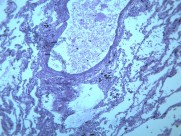

慢性支气管炎(chronic bronchitis)是由于感染或非感染因素引起气管、支气管粘膜及其周围组织的慢性非特异性炎症。其病理特点是支气管腺体增生、粘液分泌增多。临床出现有连续两年以上,每持续三个月以上的咳嗽、咳痰或气喘等症状。早期症状轻微,多在冬季发作,春暖后缓解;晚期炎症加重,症状长年存在,不分季节。疾病进展又可并发阻塞性肺气肿、肺源性心脏病,严重影响劳动力和健康。